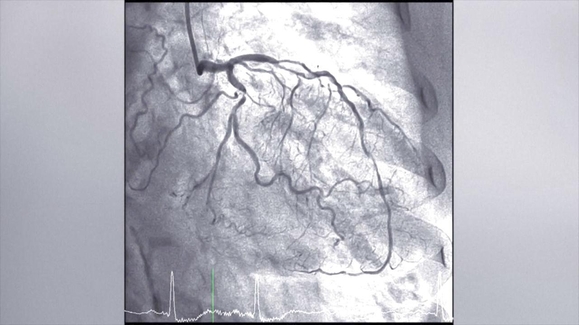

32:00Monday, Mar 02, 2026When getting winded deserves a 2nd look; TIME Names 2026 Women of the Year, Honoring 16 Global Leaders Making a DifferenceTV-PG